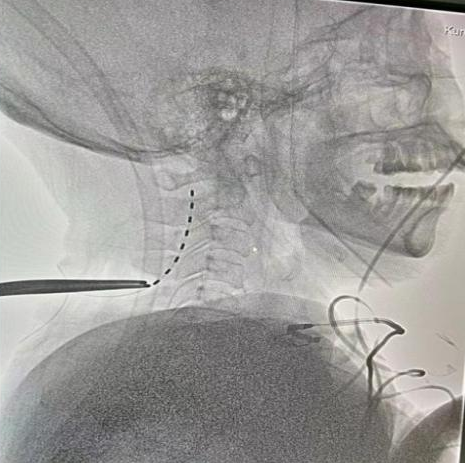

▲ST-SCS术后CT:电极位置良好

术后复查CT电极位置良好,1天后开始刺激,频率70Hz,脉宽120,电压1.5V,循环模式:15min on/15min off,工作时间8am-8pm。定期进行CRS-R评分。

目前已较为明确SCS(脊髓电刺激)对昏迷促醒是有效的,SCS(脊髓电刺激)通过手术放置刺激电极在颈髓C2-C4水平硬膜外正中部,电刺激通过上行性网状结构激活系统及丘脑下部激活系统传达到大脑皮层。ST-SCS(短时程脊髓电刺激)优点显而易见:微创、价格适宜以及早期干预。